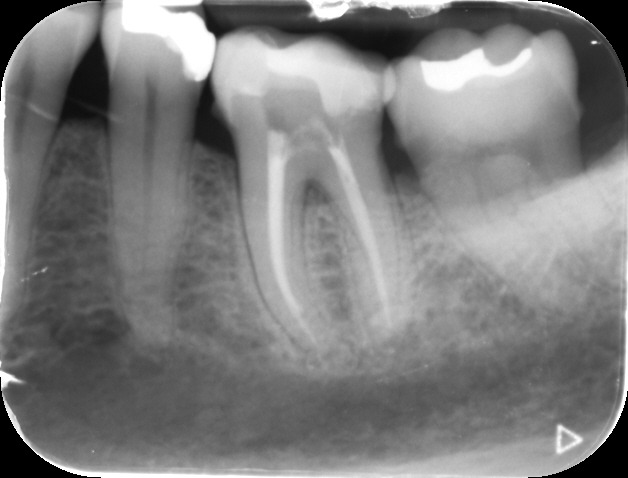

Files of different sizes are used to eliminate bacteria and infection and to shape the canals. The canals are disinfected thoroughly with irrigants and later the canals will be sealed in 3 dimensions with a special medicament called gutta-percha to prevent reinfection of the tooth and the access cavity will be sealed with a temporary filling.

After a few weeks, the tooth will be checked and when all the infection has cleared, a crown will be usually required to protect the restore the tooth to function.